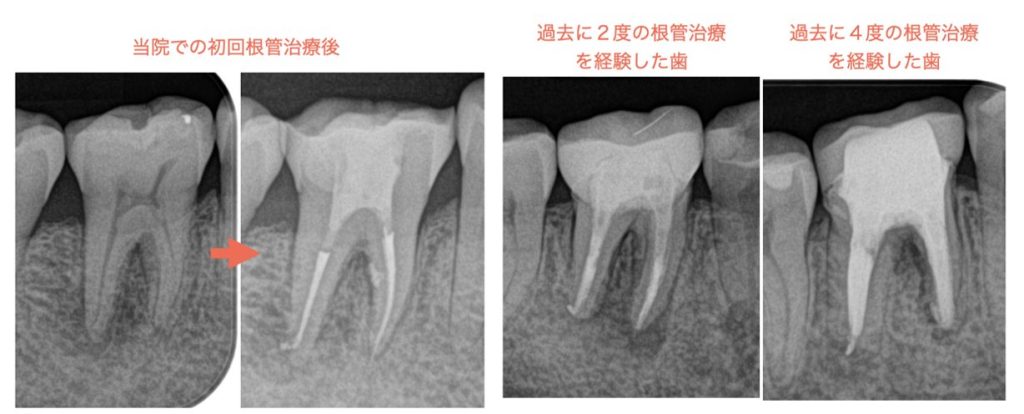

繰り返す根管治療、行き着く果ては歯根破折で抜歯

根管治療が繰り返されるごとに歯根が削られて薄くなり耐久性が低下します。歯には毎日の咀嚼や歯軋り、食いしばりなど負荷がかかりますので、耐久性が低下した歯は寿命が縮まり行き着く先は垂直性の歯根破折で抜歯となります。

初回根管治療で失敗すると再治療を繰り返すことになり歯根が薄くなります。